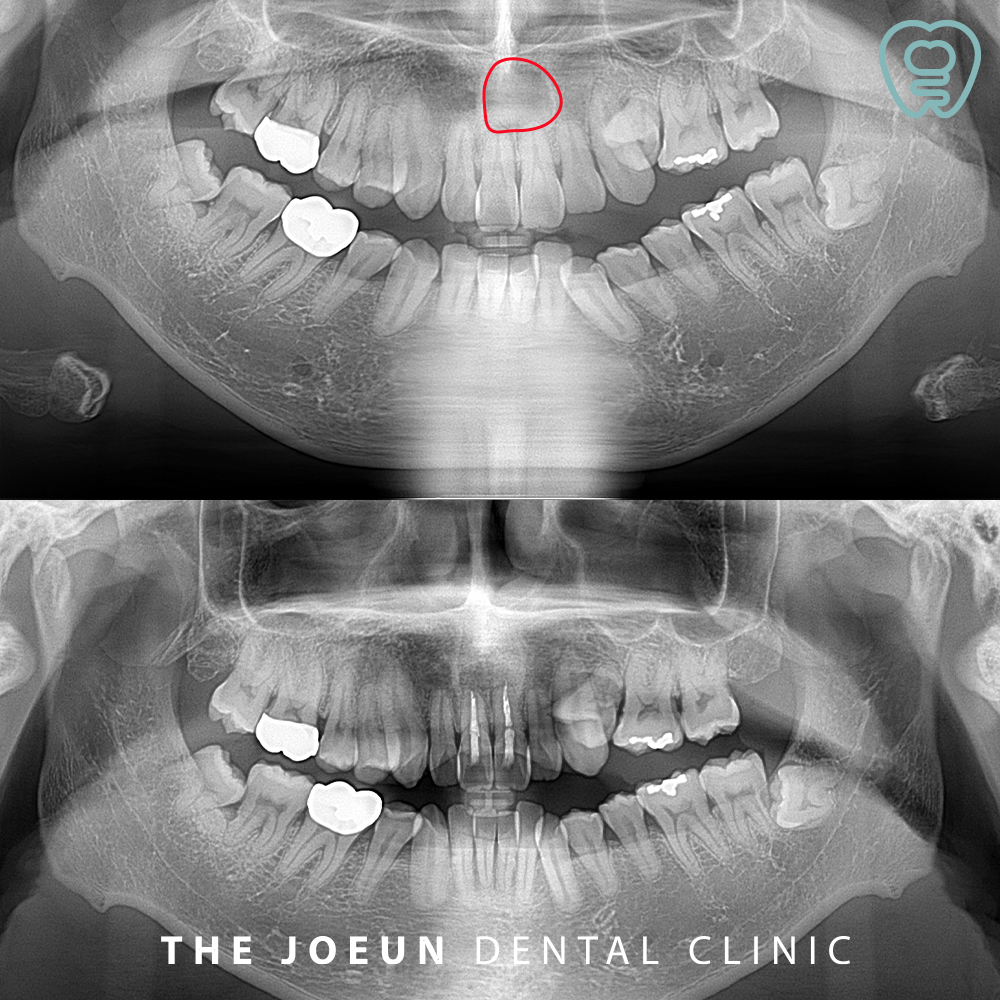

환자분께서는 입천장이 붓는 느낌이 들고 통증이 있다고 하시며 달서구치과에 내원해 주셨는데요. 파노라마를 촬영해 보았을 때, 위쪽 앞니의 뿌리 쪽으로 아주 커다란 물혹이 관찰되었는데요. 더욱 정밀한 진단을 위해 x-ray와 CT 촬영을 모두 진행하였습니다.

모든 방사선 검사에서 경계가 뚜렷이 보이는 낭종이 관찰되었고 낭종적출술을 진행하기로 계획을 수립하였습니다.